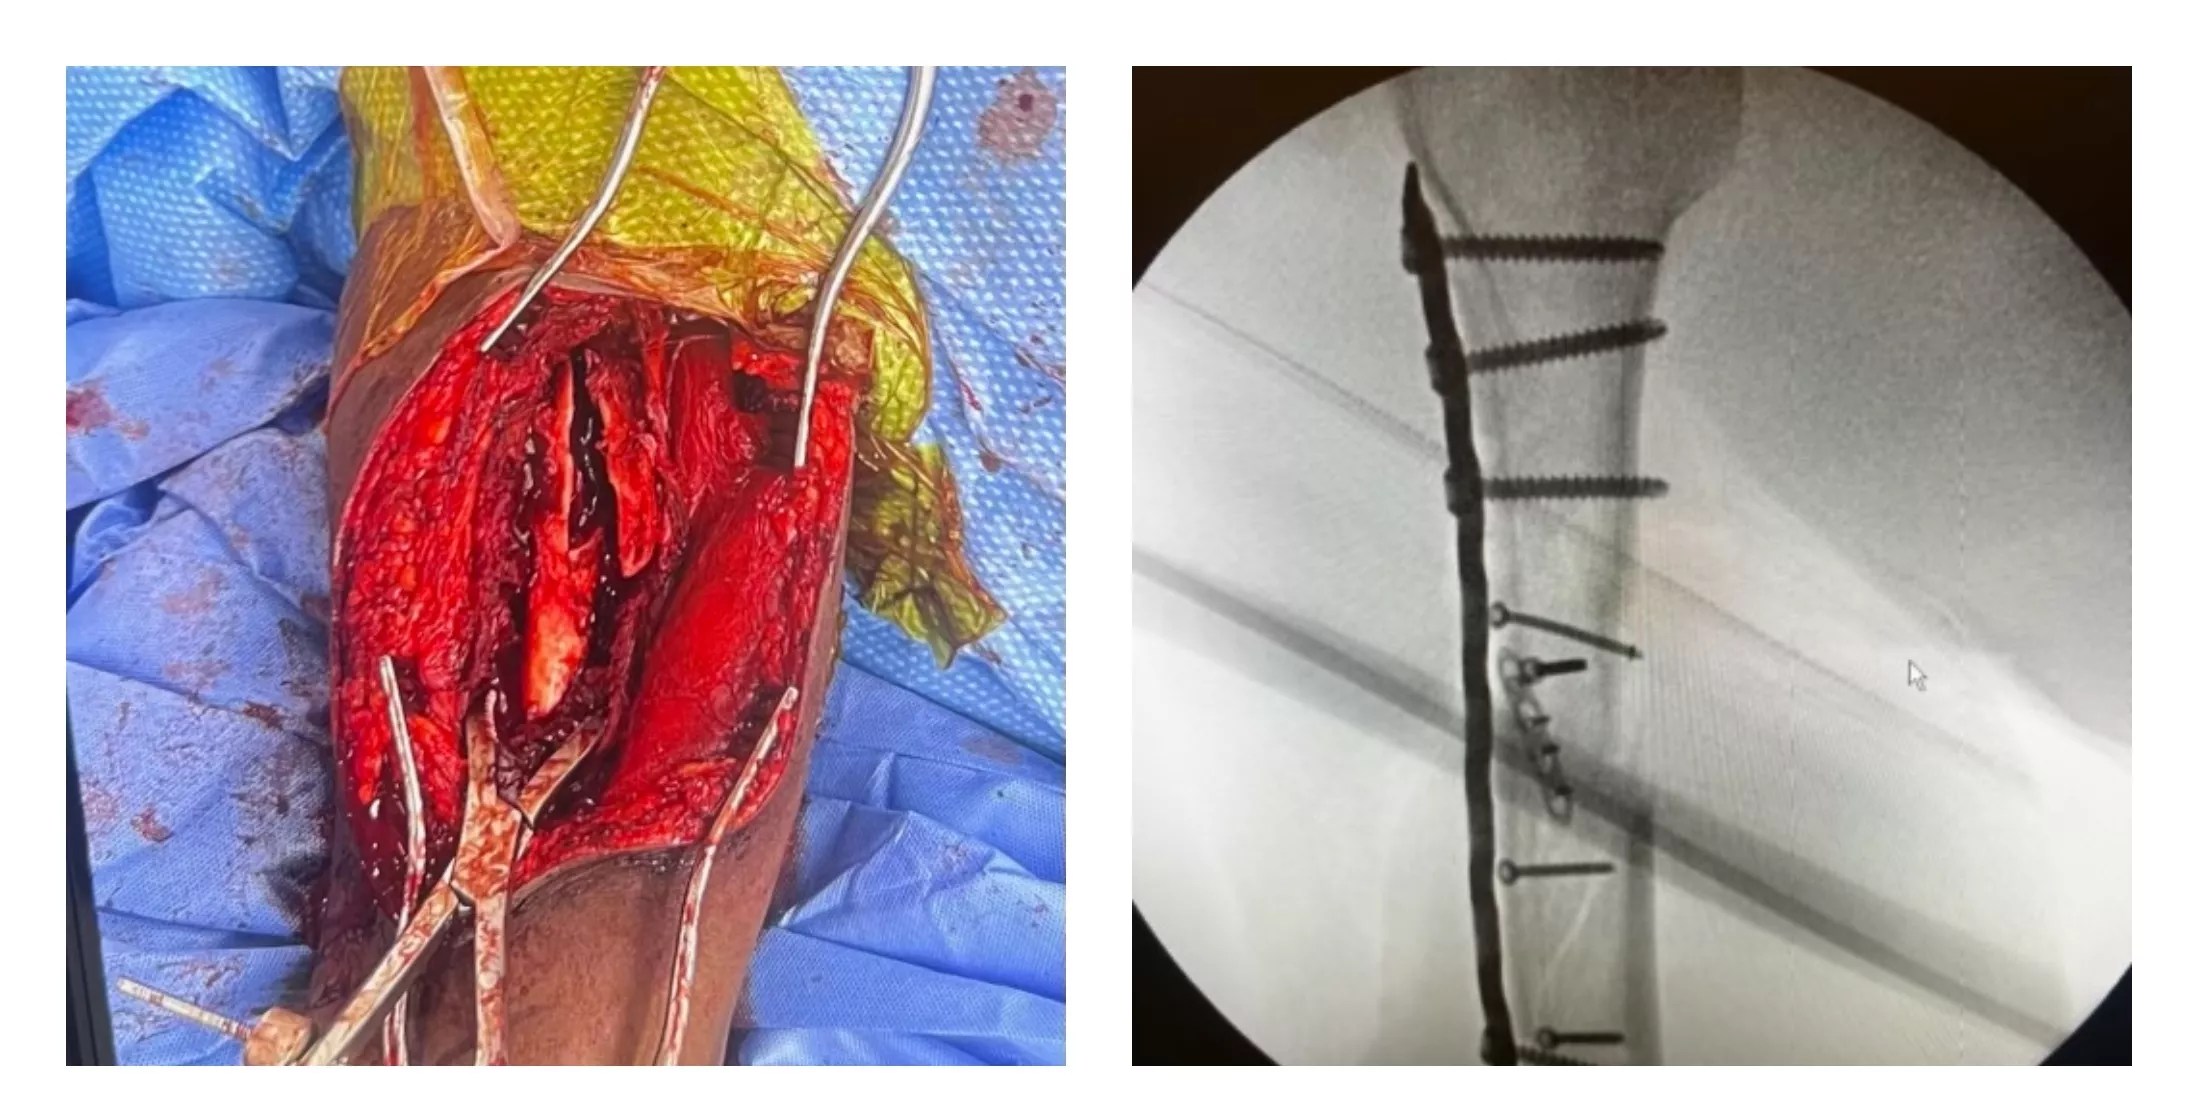

Glover doesn’t go into detail about the injuries sustained by Waddy. But bystander Weldehiwet was shot in the arm amid the chaotic scene, and the bullet did tremendous damage, as seen in the photos below.

A surgical image and an X-ray show the damage inflicted on Yekalo Weldehiwet, an innocent bystander shot by police on July 17.